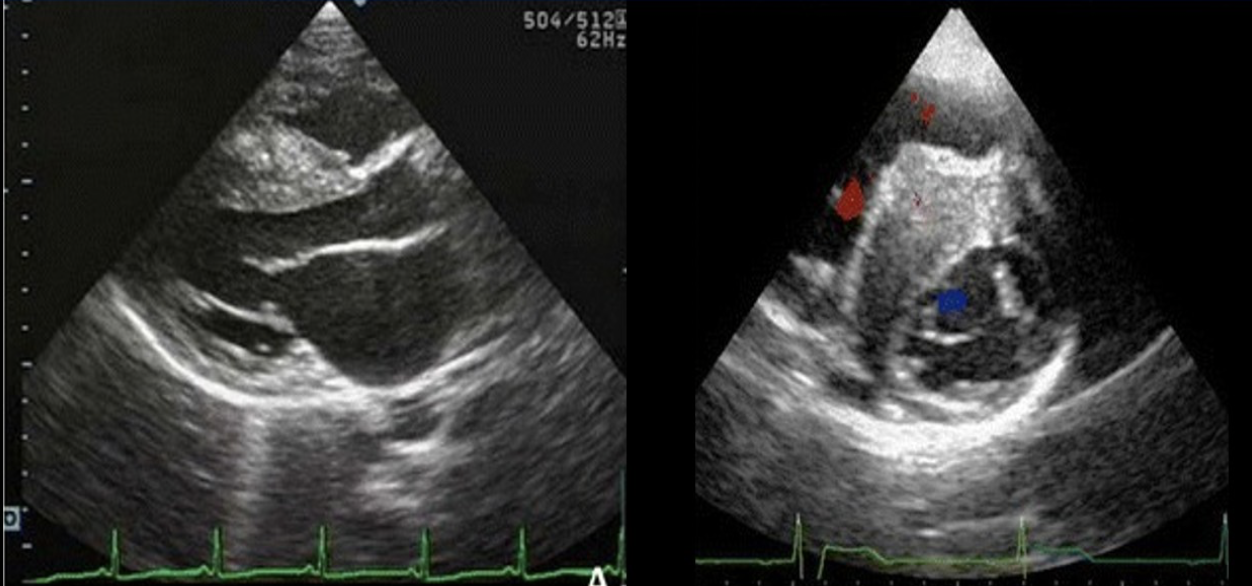

The m-mode tracing is consistent with which of the following cardiac abnormalities?

Cardiac tamponade

The image displays a focal wall structure and motion abnormality caused by?

Focal HCM

Which of the following describes the appearance of a mild pericardial effusion?

< 1 cm fluid located posterior to the heart

Which of the following is present not he image?

Mild pericardial effusion and moderate pleural effusion